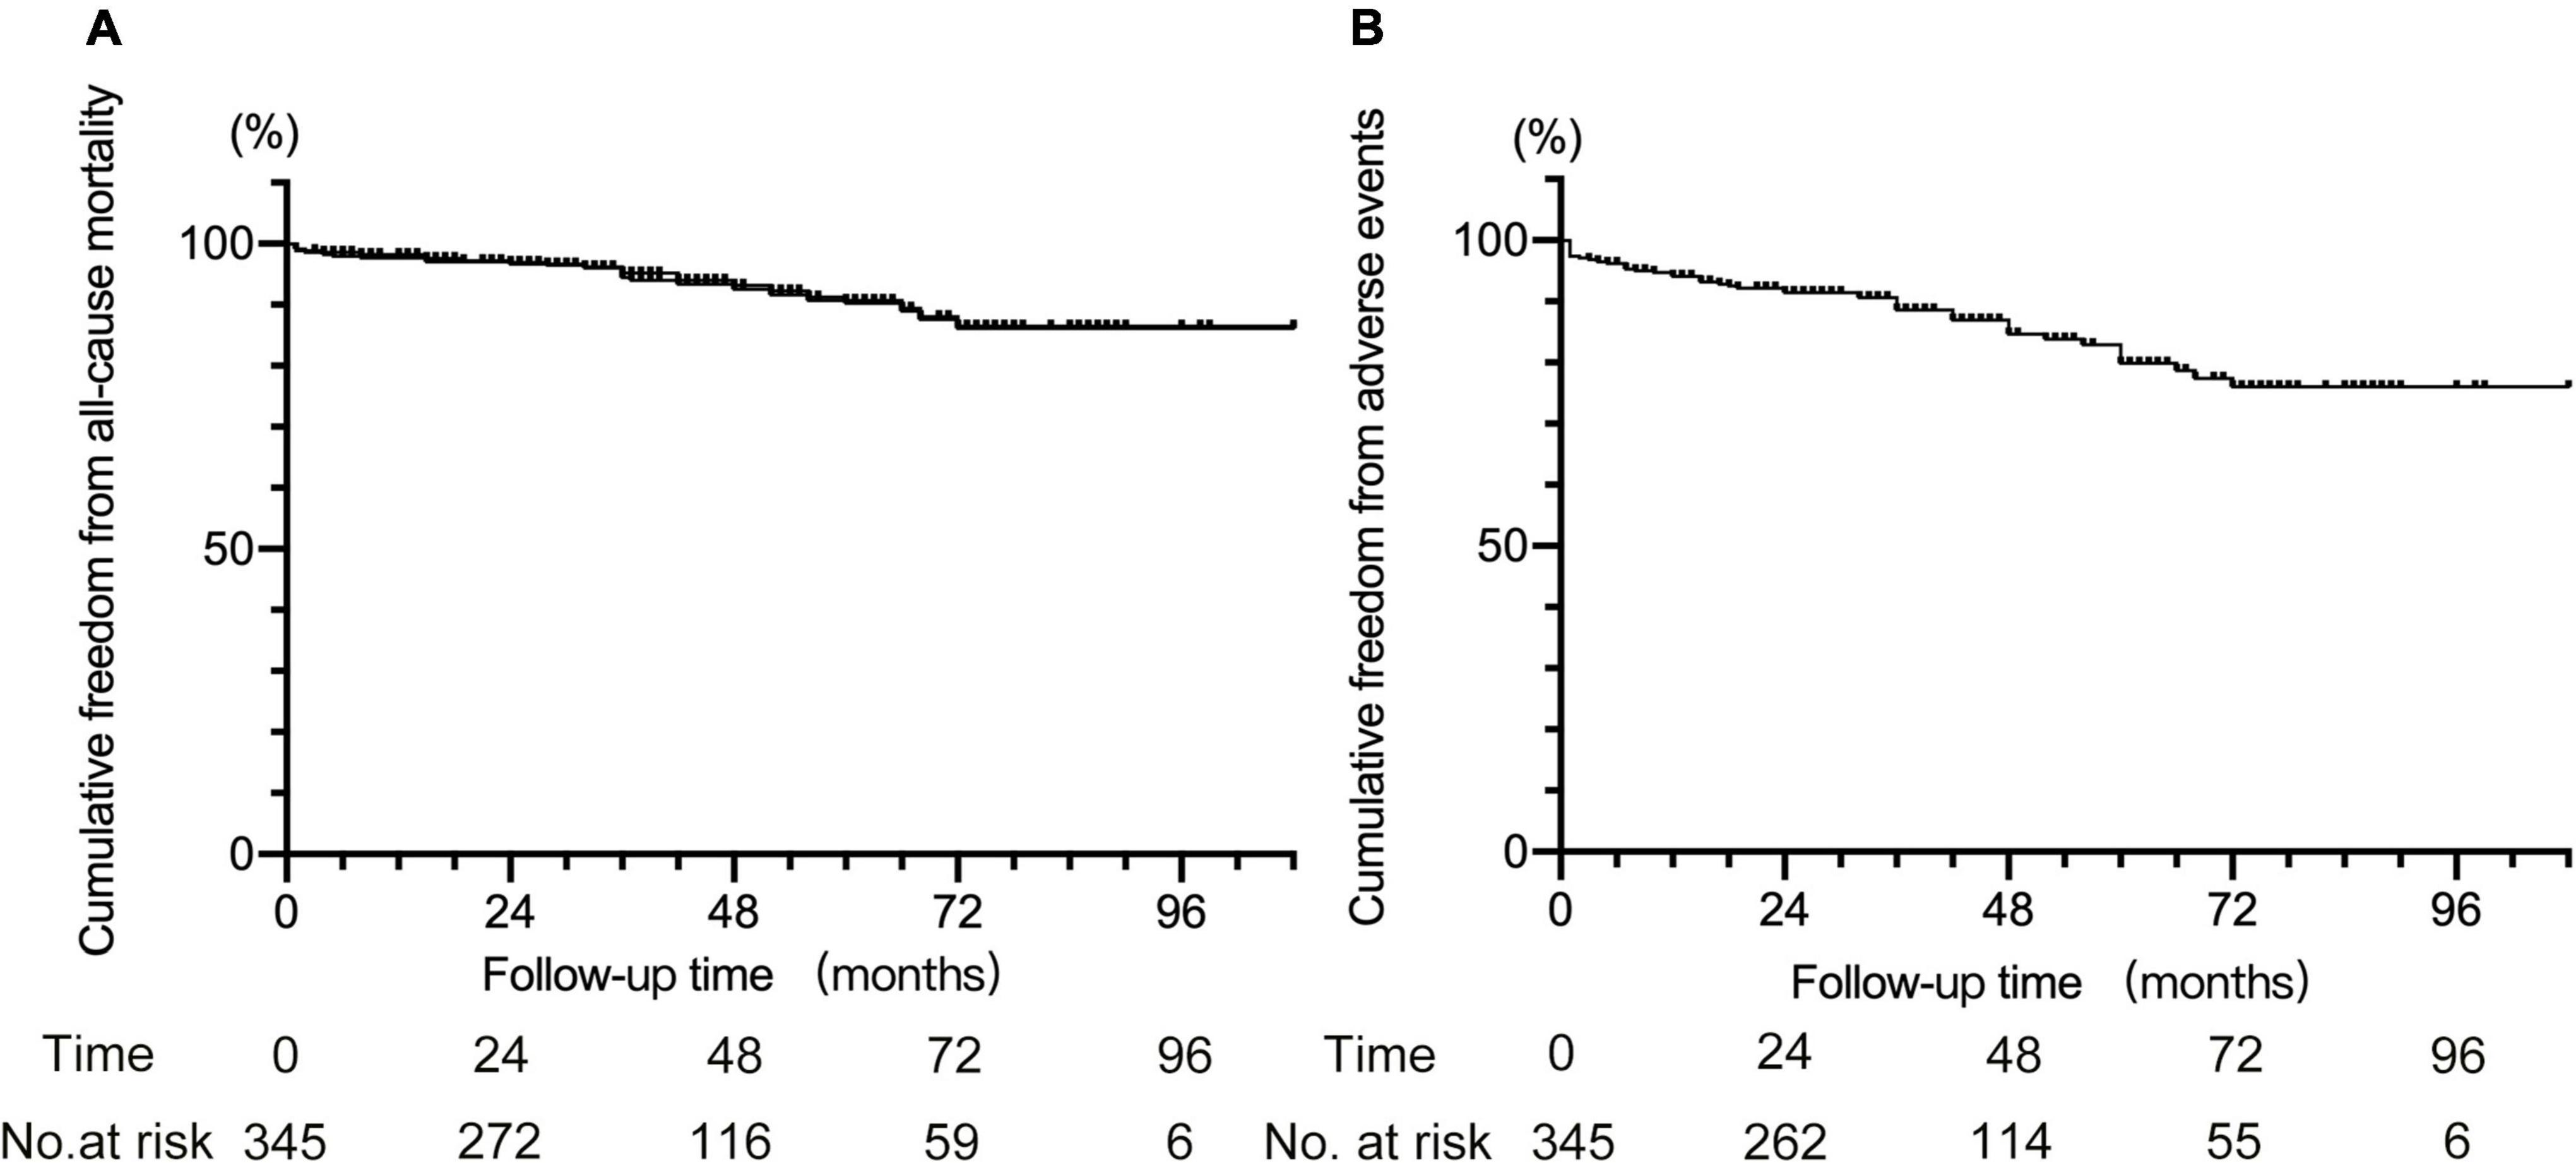

Results: Among the 345 patients, 278 (80.6%) received single chimneys, 53 (15.4%) received double chimneys, 7 (2%) received triple chimneys, and 7 (2%) underwent cTEVAR accompanied by other techniques (two with extra-anatomical bypass, two with in situ fenestration, and three with physician modified fenestration). A total of 412 chimney stents were used, including 27 in the innominate artery (IA), 113 in the left common carotid artery, 270 in the left subclavian artery, and two in the aberrant right subclavian artery. Early type IA endoleaks were found in 38 (11%) patients, including 12 with the double or triple chimney technique. Early type II endoleak was found in nine (2.6%) patients. Early re-intervention occurred in two patients with double chimney technique, one for chimney stent migration and the other for compression of chimney stent. The 30-day mortality was 1.2% (4 in 345). During a mean follow-up of 42 ± 22 months (range 1–108 months), major stroke occurred in nine (2.6%) patients, chimney occlusion or stenosis occurred in six (1.7%), and retrograde type A aortic dissection occurred in four (1.2%). Fourteen (4.1%) patients received the secondary intervention. The all-cause mortality was 6.7% (23 in 345). Additionally, the total adverse event rate after cTEVAR was 13.9% (48 in 345).

Statistical analysis

Descriptive statistics were used to describe patient data and outcomes in this cohort. Continuous data are expressed as mean ± SD or median (range), and categorical data are given as the counts (percentage). The Kaplan–Meier analysis was used to establish the rate of freedom from all-cause death and freedom from all adverse events). P < 0.05 was considered statistically significant. Statistical analysis was conducted using GraphPad 7 (GraphPad Software, Inc., San Diego, CA, United States).

For other adverse events, nine patients had major cerebral infarction, among whom three occurred within 30 days after TEVAR. Furthermore, one patient who underwent cTEVAR with IA and LCCA chimney stents deployed had chest pain 42 months after TEVAR. The CTA revealed migration and partial disintegration of the aortic stent (Supplementary Figure 4), and the patient died due to aortic rupture. A total of 23 deaths were recorded, including 4 that occurred within 30 days after TEVAR. The causes of later death after TEVAR included aortic rupture in four, cerebral infarction in two, cerebral hemorrhage in two, myocardial infarction in one, pulmonary infection in one, pulmonary hemorrhage in one, cancer in two, and six patients died for unknown reasons. The all-cause mortality rate was 6.7% (23 in 345), with 5.4% (15 in 278) in patients with single chimneys and 13.3% (8 in 60) in patients with double or triple chimneys (5.4 vs. 13.3%, P < 0.05). Collectively, the adverse events occurred in 13.9% of all the patients (48 in 345), and the rate was 11.5% (32/278) in patients with single chimney while 26.7% (16 in 60) in patients with double or triple chimneys (11.5 vs. 26.7%, P < 0.05). There was no death or adverse event observed in the seven cases receiving cTEVAR with other techniques. The Kaplan–Meier curves for cumulative freedom from all-cause death and from post-cTEVAR adverse events were shown in Figure 3.

Figure 3. Kaplan–Meier curve for cumulative freedom from all-cause death (A) and from adverse events (B) after cTEVAR.